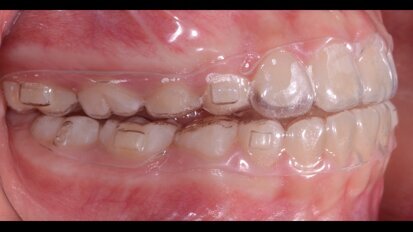

Allineatori trasparenti: uno studio esamina la perdita di ancoraggio durante la distalizzazione del molare superiore

ROMA, Italia: Nel tentativo di colmare una lacuna nella letteratura, i ricercatori hanno analizzato la perdita di ancoraggio del premolare e del canino che ...